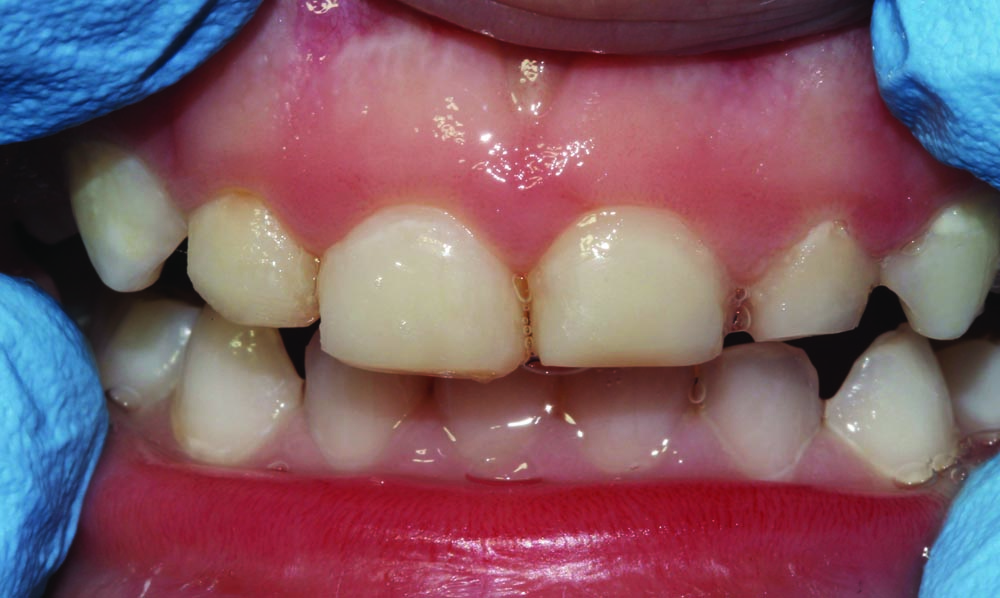

A shy and apprehensive 3-year-old female patient presented with multiple caries in all quadrants. To keep the patient's in-office experience positive, all posterior teeth were restored with a combination of atraumatic restorative techniques and minimally invasive techniques.

Maxillary anterior incisors #52–#62 (D–G) all exhibited varying depths of decay and required restoration (Fig. 6). Only topical anesthetic was used, and the area was isolated with cotton rolls. Teeth were minimally prepared into enamel only with an NSK high-speed handpiece and a tapered rough grit diamond FG bur.